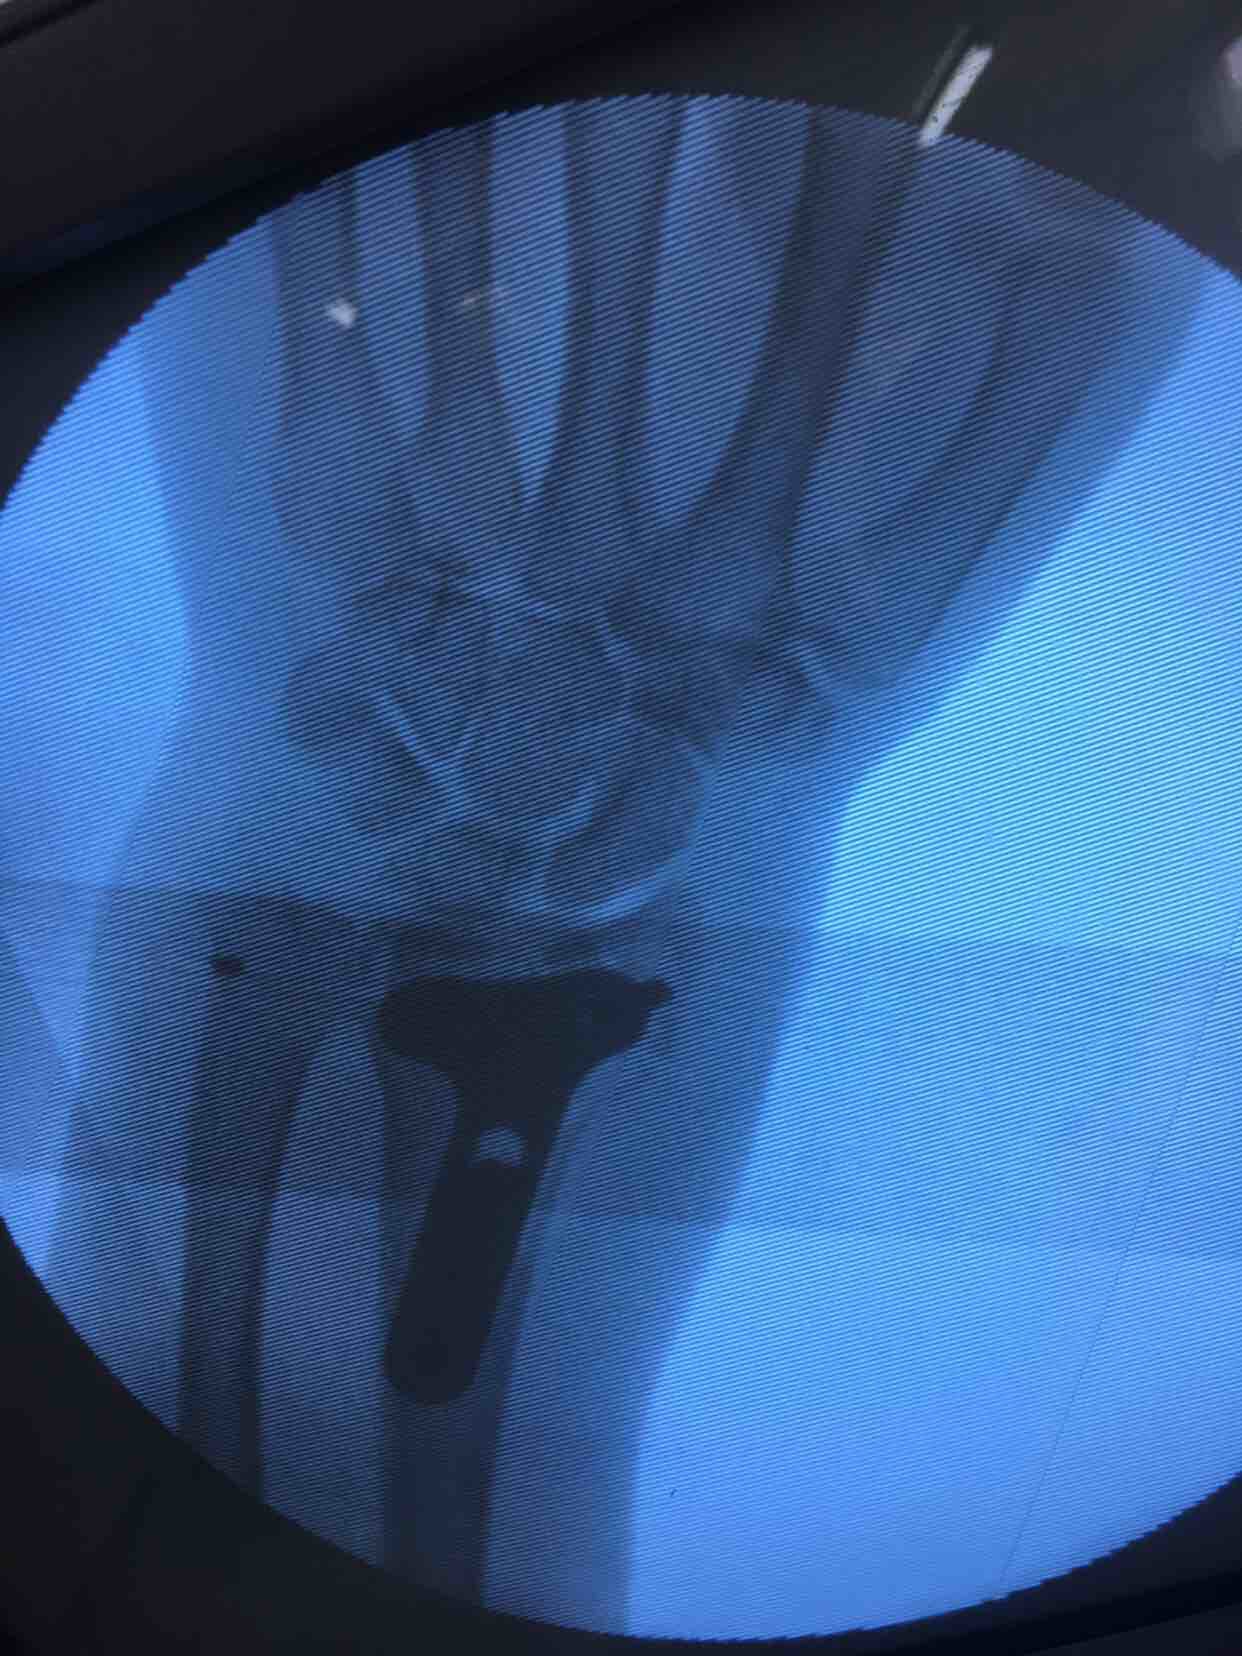

摔伤后腕部肿痛,活动受限4天入院。4天前在外院行手法整复,复查关节面塌陷,尺偏角掌倾角变小,后来我院就诊。

诊断:右侧克雷氏粉碎性骨折完善术前准备,在臂丛麻醉下行切复内固定术,术后抗炎,消肿等对症处理。